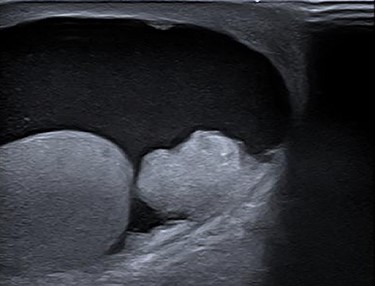

Colonoscopy revealed a polyp in the sigmoid colon and an obstructing tumor suspected for CRC (20 cm from the anal verge) (Fig. 1). An abdominal contrast-enhanced computed tomography showed four lesions in the liver suspected for metastases without lymphadenopathy (Fig. 2). Magnetic resonance of the liver showed five lesions suspected for metastases. Chest X-ray was normal.

Abdominal contrast-enhanced computed tomography. A. Tumor in the sigmoid colon. B. Four hypodense lesions in liver suspected for metastases.